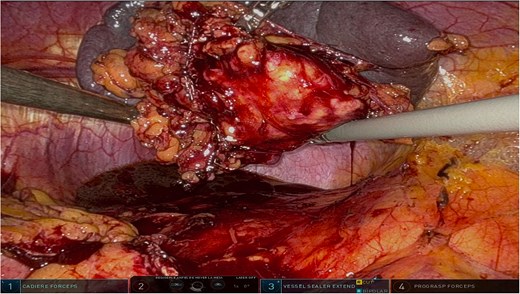

The surgery was performed using the Da Vinci robotic system under general anesthesia. The patient was positioned supine with reverse Trendelenburg. Four robotic trocars and one assistant trocar were placed. The gastro-splenic ligament was dissected to expose the distal pancreas, and the pancreas was transected using a linear stapler, ensuring tumor-free margins (Fig. 2). The splenic artery and vein were individually ligated with robotic sutures, and the spleen was mobilized and removed along with the pancreas (Fig. 3). The specimen was extracted via mini-laparotomy and sent for histopathological analysis (Fig. 4).

Intraoperative view showcasing the dissection and mobilization of the greater curvature of the stomach. This involved dividing the gastrocolic ligament to expose the retroperitoneal space, providing access to the distal pancreas while preserving surrounding structures to minimize surgical trauma.